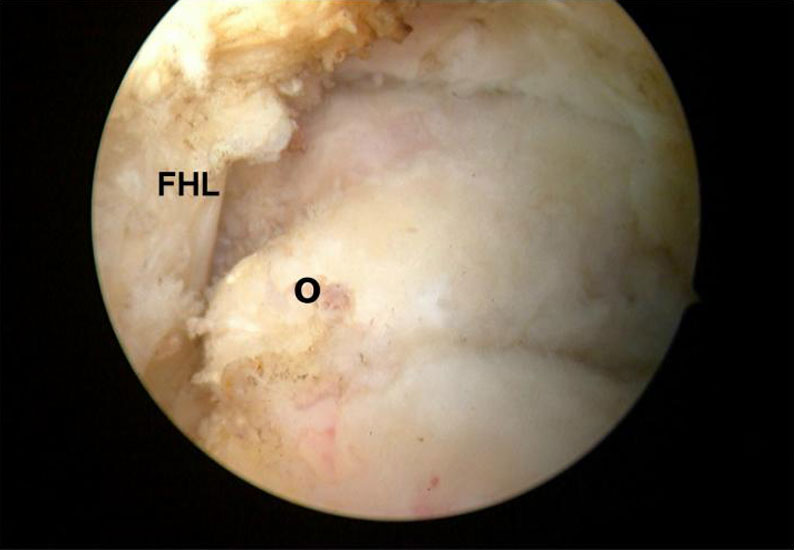

Es wird zunächst ein Weichteildebridement durchgeführt, bis die Flexor hallucis longus-Sehne identifiziert werden kann. Während des Debridements sollte auf die korrekte Ausrichtung der Instrumentenöffnung nach lateral geachtet werden. Im Verlauf empfiehlt sich der Wechsel auf eine bipolare Ablationselektrode, die eine gezielte Freilegung der Strukturen unter gleichzeitiger Blutstillung ermöglicht, ohne dabei unkontrolliert Gewebe anzusaugen (rechte Seite, m=medial, l=lateral). Das Os trigonum bzw. die Osteophyten sowie die FHL-Sehne müssen vollständig dargestellt werden (*=Os trigonum, FHL=Flexor hallucis longus-Sehne).

Abbildung Nr. 11-13

Das Os trigonum wird aus dem Weichteilgewebe gelöst und anschließend mit einer Fasszange entfernt. Bei größeren Knochenfragmenten muss ggf. das mediale Arthroskopieportal um wenige Millimeter verlängert werden, um die Extraktion zu ermöglichen. Nach Resektion des Os trigonum ist die posteriore Facette des Subtalargelenks erkennbar (rechte Seite, PF=posteriore Facette, FHL=Flexor hallucis longus-Sehne, T = Talus, K = Kalkaneus, *=Os trigonum).